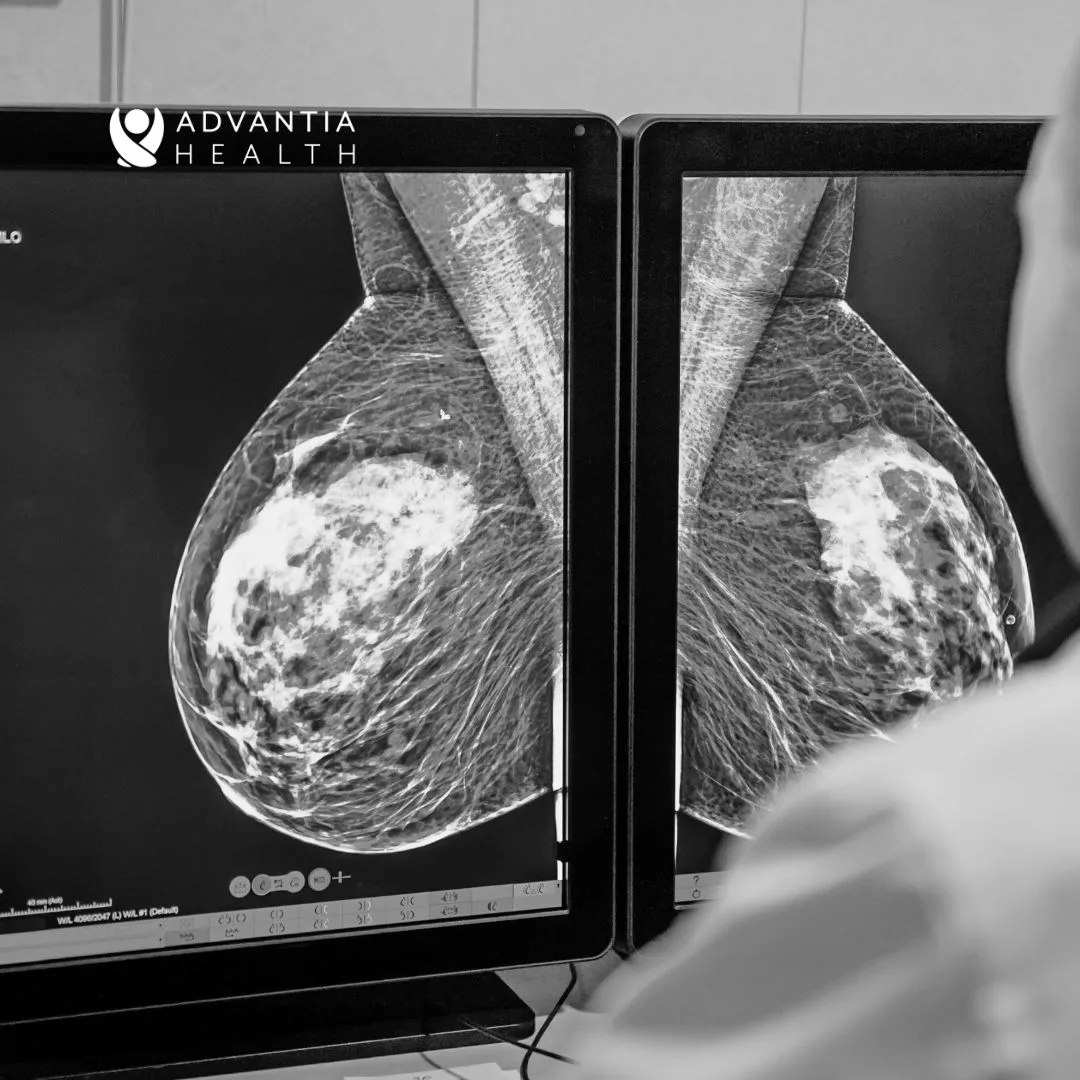

The history of imaging technology began with traditional screening mammography, which involved the use of X-ray films to capture images of the breast. While this was an important step forward in early breast cancer detection, the technology had limitations, particularly in imaging dense breast tissue. As the need for more accurate and detailed imaging became evident, the transition to digital mammography marked a significant milestone. Digital mammography brought forth clearer and more precise images, enhancing the ability to detect abnormalities in breast tissue.

Subsequently, the development of digital breast tomosynthesis (DBT) presented a groundbreaking shift in mammography technology. Unlike traditional mammography, DBT captures multiple images of the breast from different angles, reconstructing a three-dimensional image of the breast tissue. This advancement has been particularly beneficial for women with dense breast tissue, as it significantly reduces the overlapping of breast structures that could potentially obscure early signs of breast cancer.

One of the key advances is digital breast tomosynthesis, which provides three-dimensional images, enhancing the clarity of breast tissue and reducing the superimposition of structures and artifacts that can sometimes obscure abnormalities. Another critical development is contrast-enhanced MRI and breast ultrasound, which are particularly useful for women at high risk or those with dense breast tissue. Additionally, contrast-enhanced mammography has emerged as a promising technology to reduce false positives, improving accuracy in breast cancer detection.